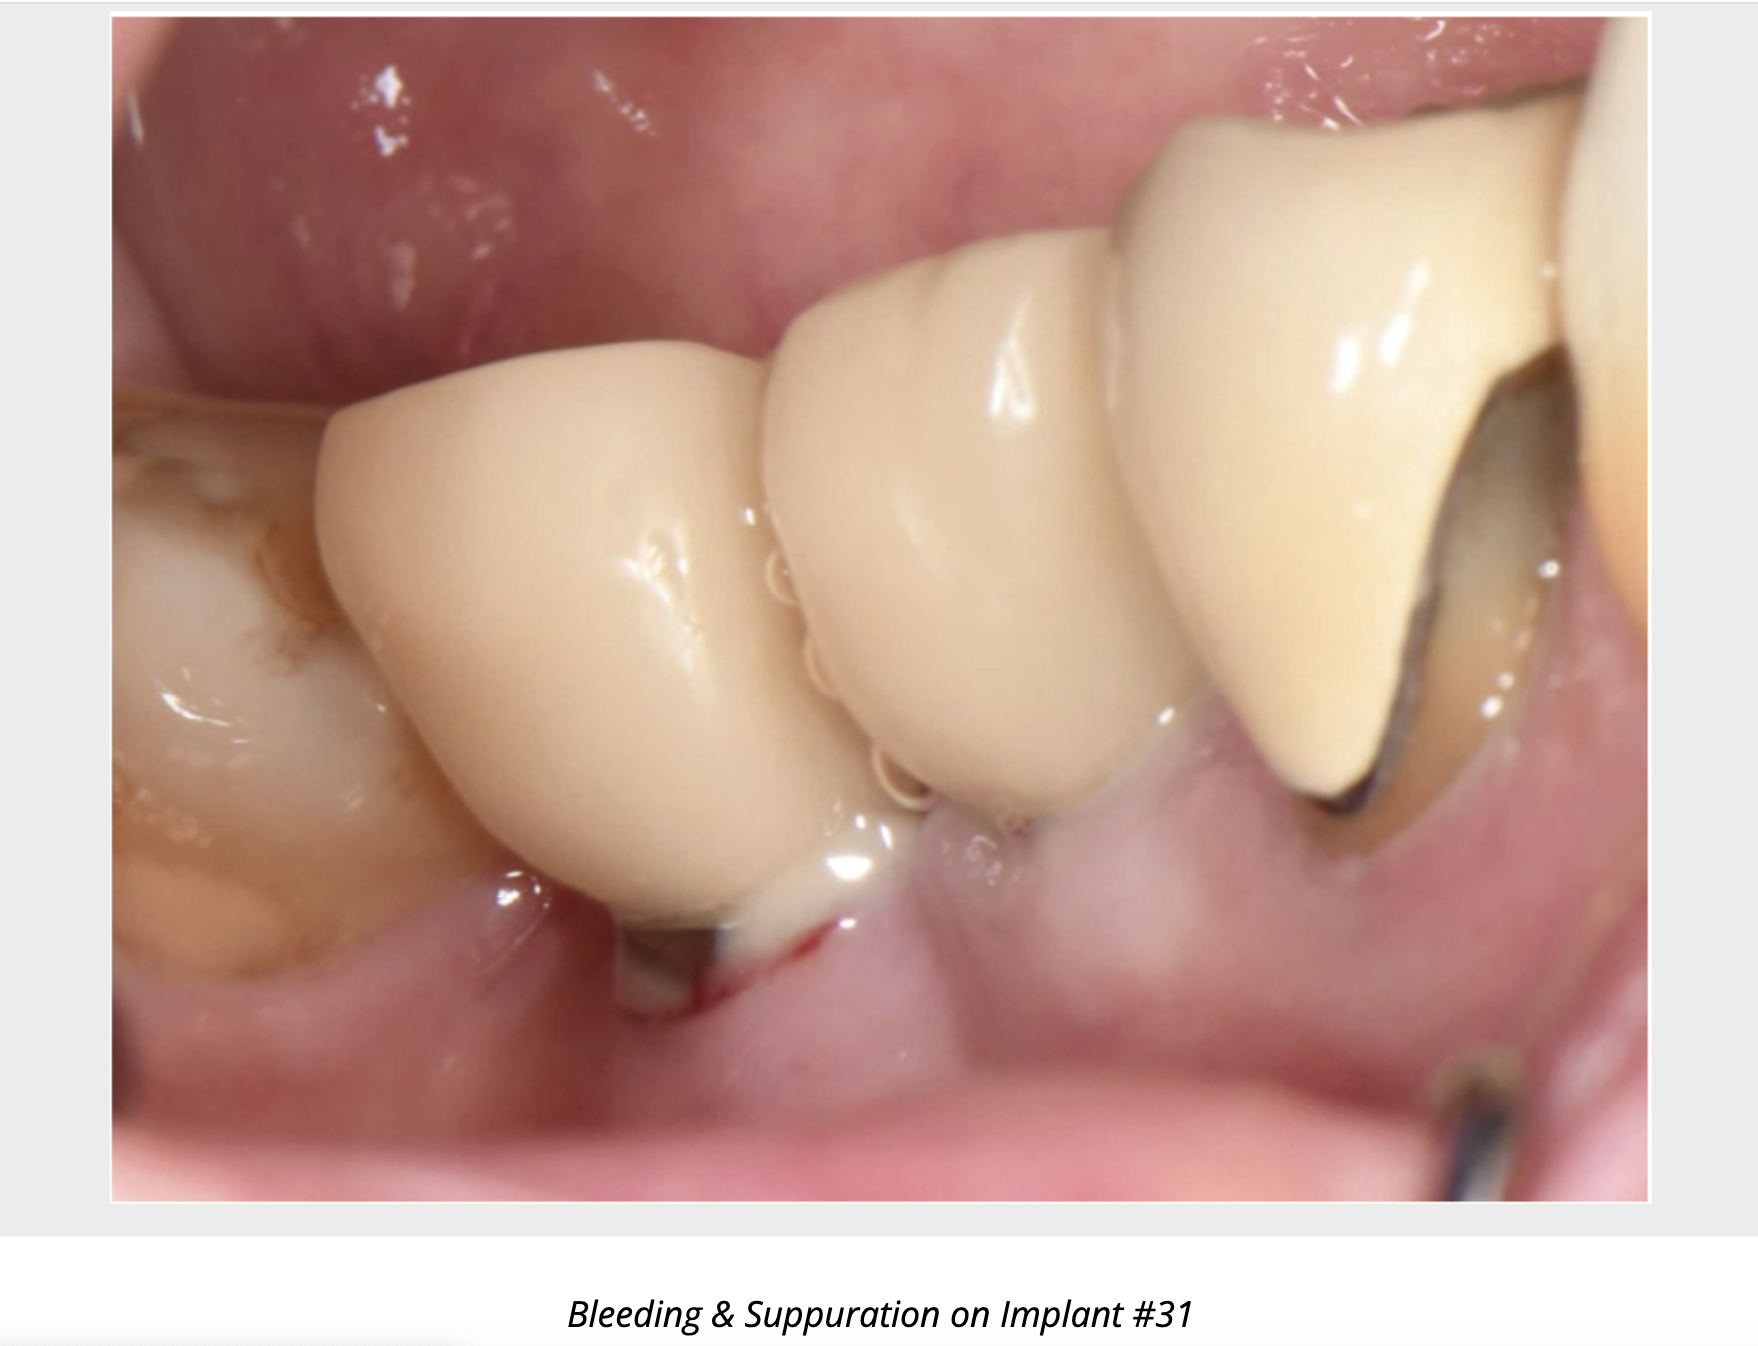

Prompt treatment at the first clinical signs of peri-implant mucositis—bleeding on probing, erythema, swelling, or suppuration —can prevent complex and costly peri-implantitis treatment down the road. Early collaboration allows us to address reversible inflammation, optimize risk factors, and implement individualized maintenance protocols, helping to protect your patients’ implants and long-term oral health.